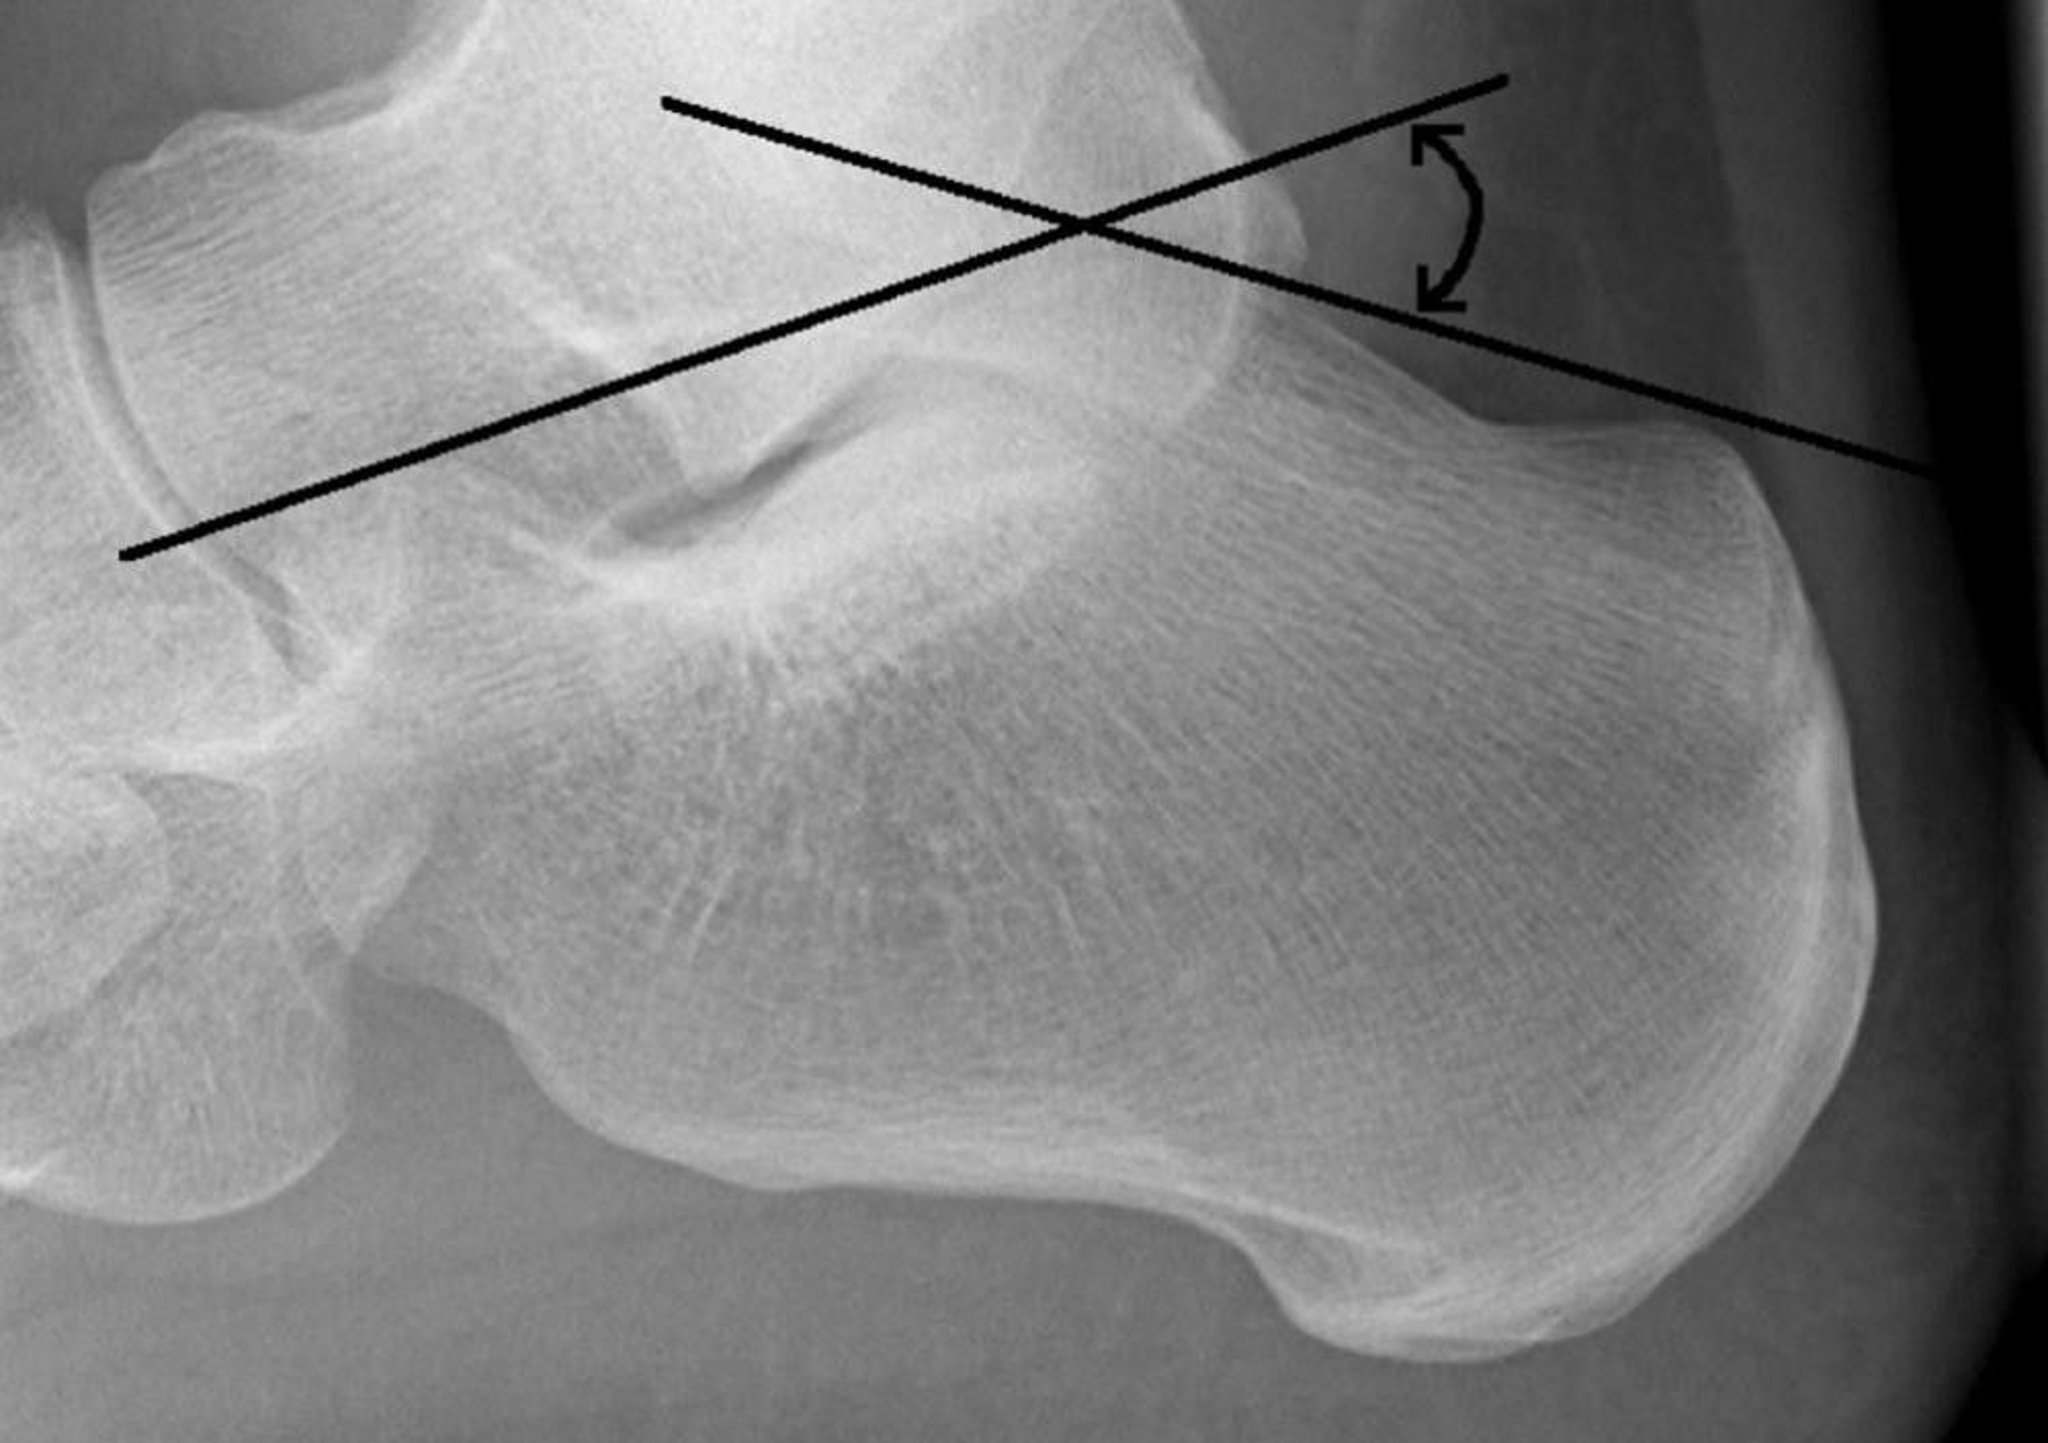

Bohler Angle

The Bohler angle is formed by the intersection of a line drawn from the superior aspect of the posterior calcaneal tuberosity to the superior subtalar articular surface and a line drawn from the superior subtalar articular surface to the superior aspect of the anterior calcaneal process. Normally, the angle is 20 to 40°. An angle of < 20° suggests a fracture.

Image courtesy of Danielle Campagne, MD.